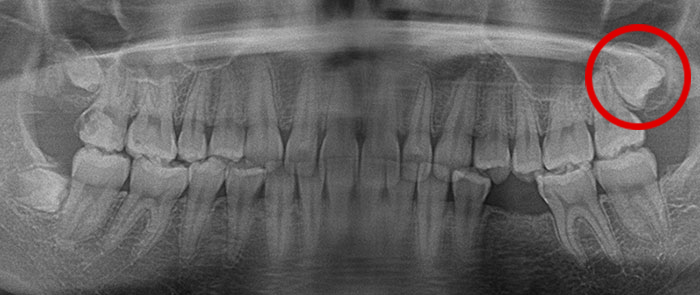

歯の移植の症例

Before

After

親知らずの歯を移植したケースです。患者様はとても喜ばれておりました。